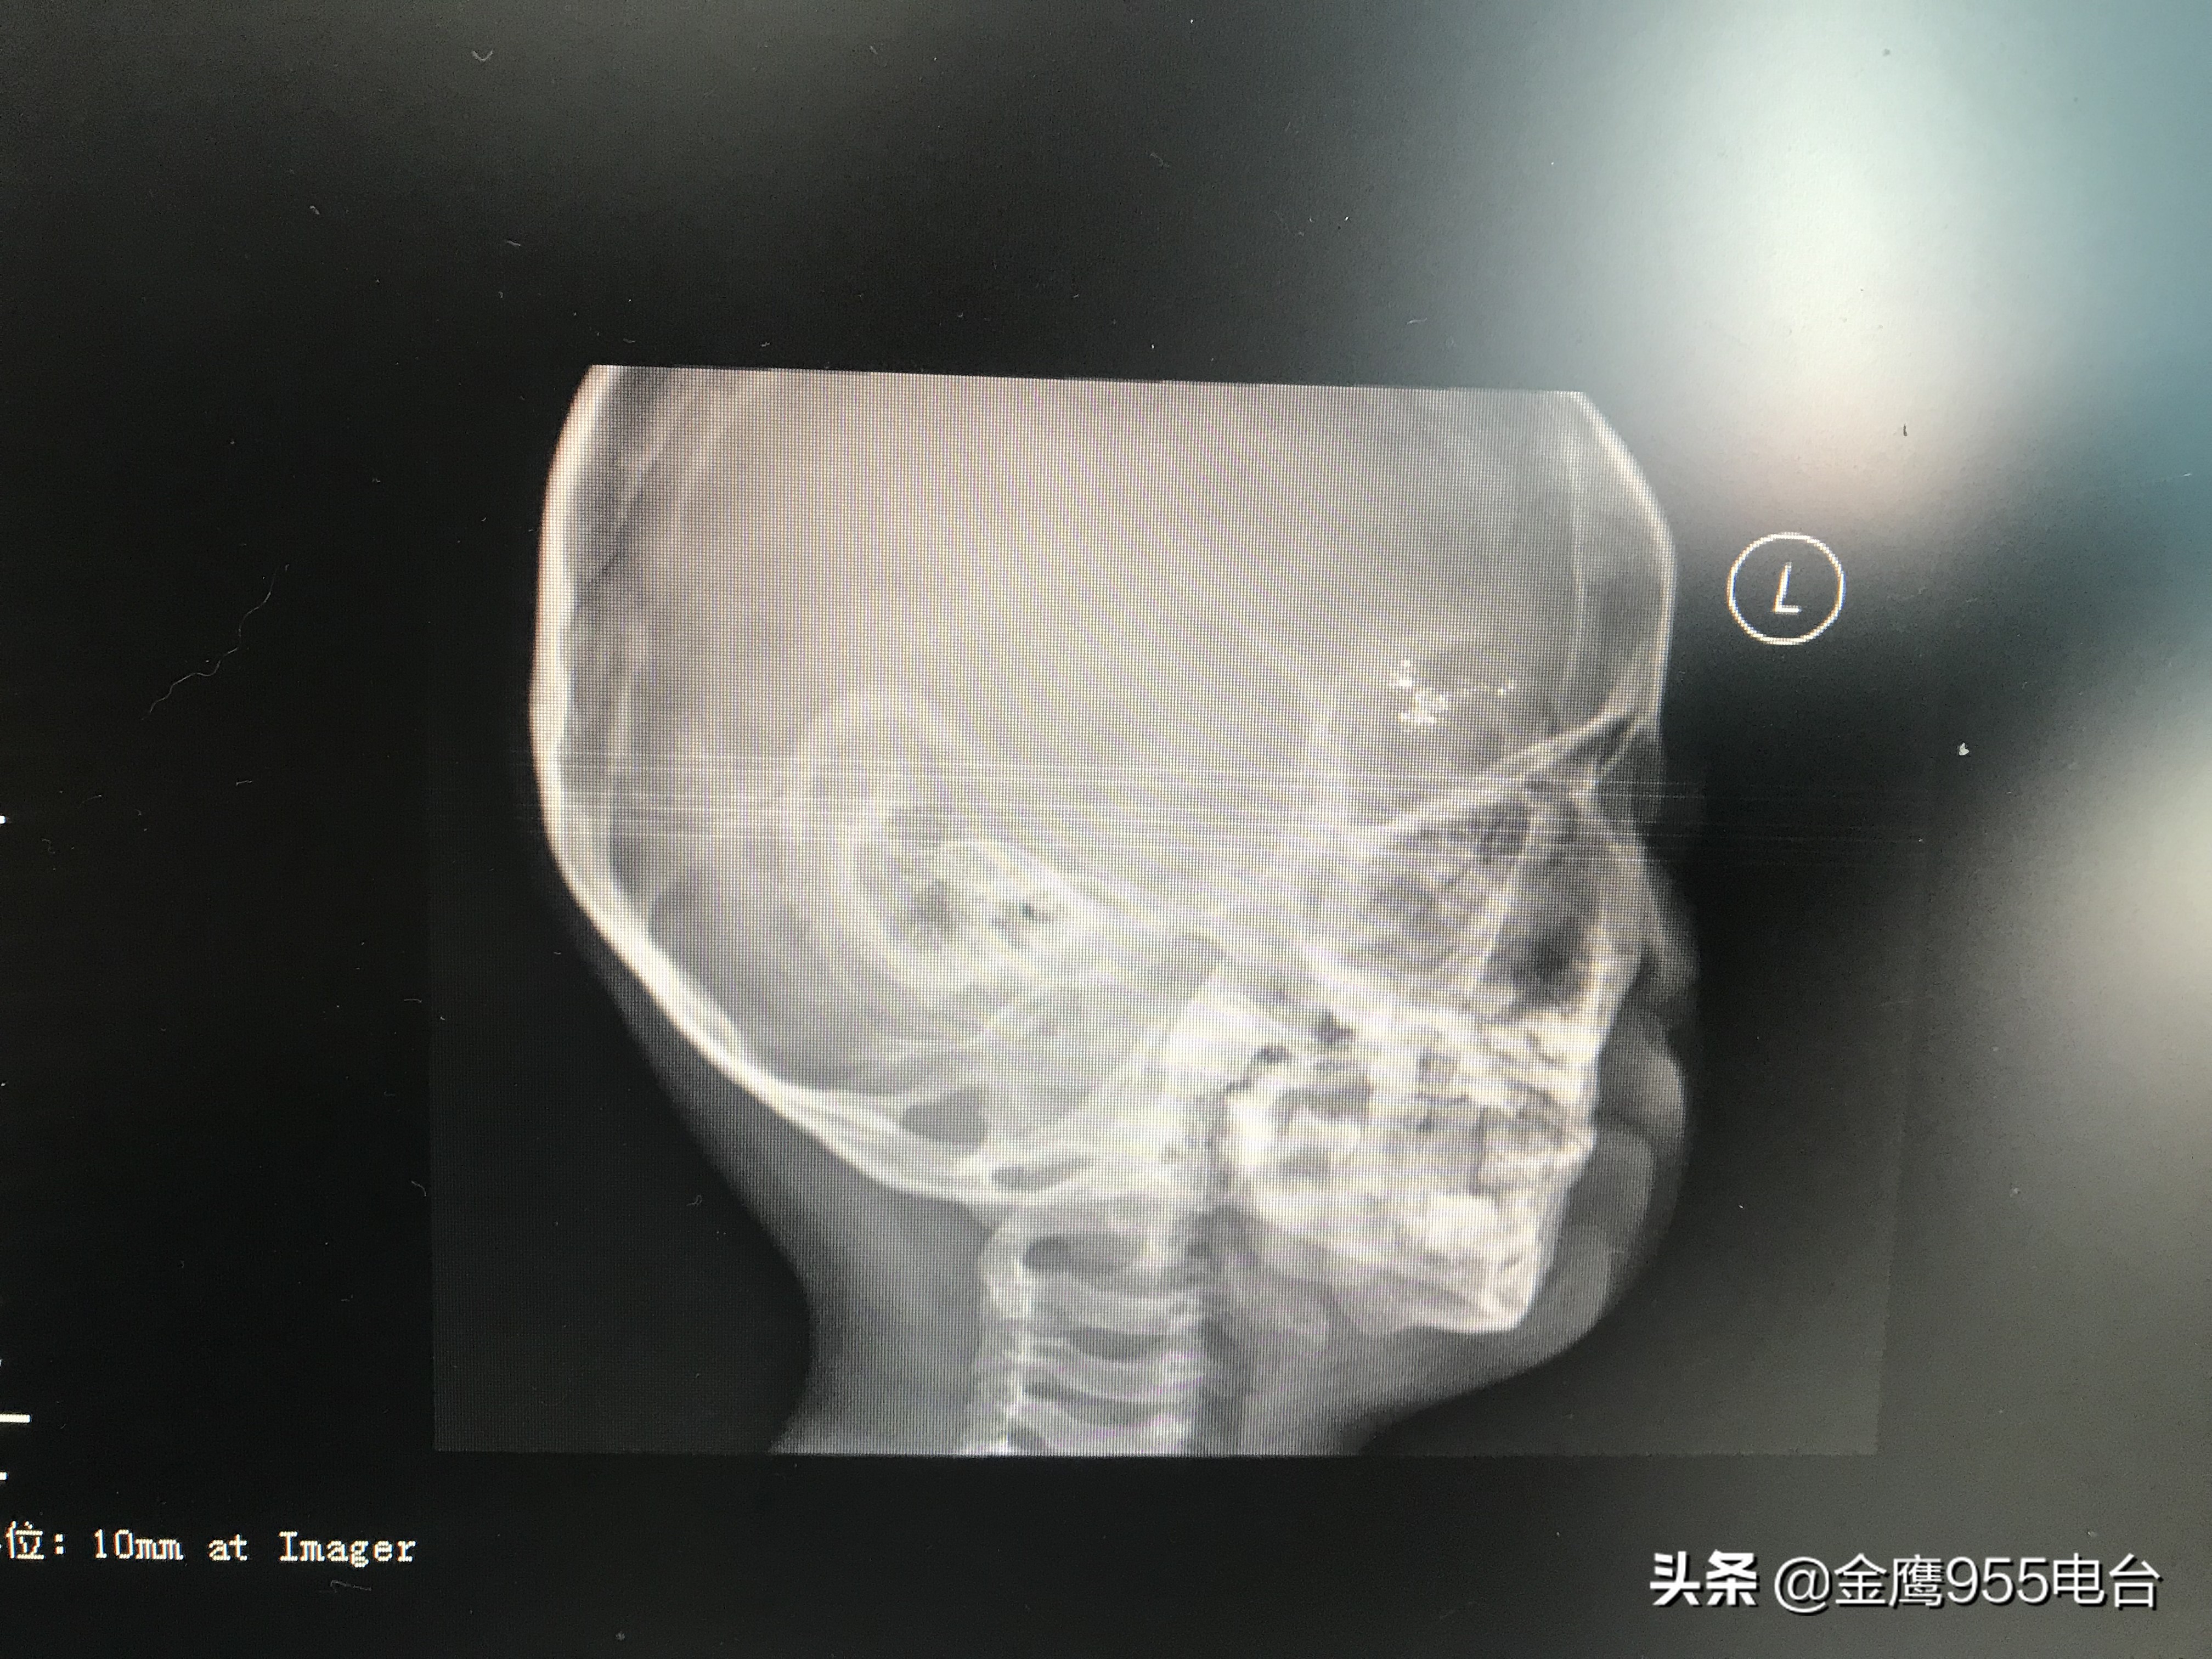

“这是他的颅脑CT,可以看到还是有一个高密度的阴影,如果这个汞珠不取出来的话,会对小孩的中枢神经发育、肾脏、性格方面都有影响。比如这个小孩,已经出现好动,有攻击性的行为。”湖南省职业病防治院职业病一科副主任医师袁娟告诉记者,正常人体内的尿汞含量在4微克每克肌酐左右,然而小智体内的尿汞含量最高达到了737微克每克肌酐,超过正常水平近两百倍。由于汞珠残留的位置靠近颅脑,不能够通过手术直接将残留在小智体内的汞珠取出。最终医院决定,利用药物加速汞珠的自由排出过程。经过三年的驱汞治疗,小智的尿汞含量已经降落到了正常人体水平的四十倍左右。